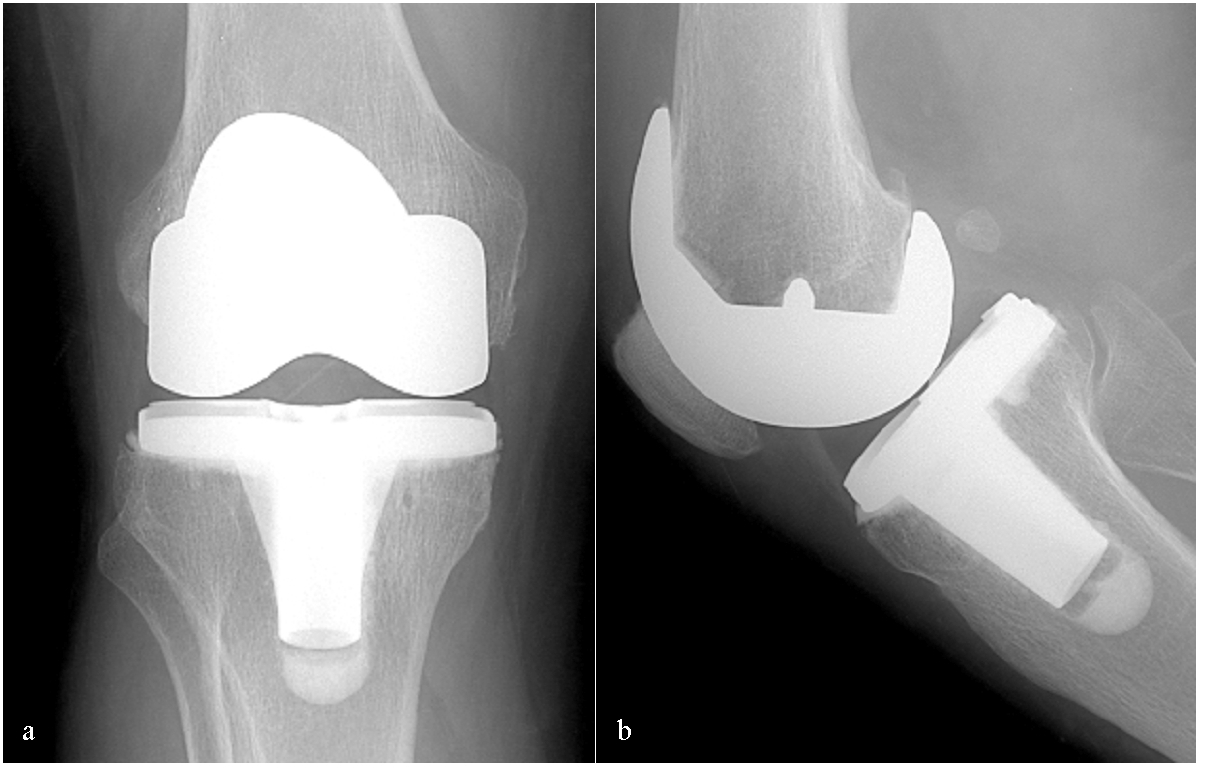

Después De Una Prótesis De Rodilla Cuando Se Puede Conducir, ¿ En cuanto puedo caminar normal después de una prótesis de rodilla, 421.88 kB, 00:18, 13,806, Dr. Nicolás Valladares, 2020-07-04T22:42:51.000000Z, 3, Especialista Protesis de Rodilla - Sportme Sevilla, clinicabernaldez.com, 2560 x 1876, jpeg, WebEl tiempo medio de recuperación después de una operación de prótesis de rodilla es de dos a tres meses. Uno de los hitos clave durante la recuperación de una prótesis de rodilla. , 20, despues-de-una-protesis-de-rodilla-cuando-se-puede-conducir, Novedades y Muebles WebEl tiempo medio de recuperación después de una operación de prótesis de rodilla es de dos a tres meses. Uno de los hitos clave durante la recuperación de una prótesis de rodilla.

Prótesis de Rodilla – Dr. Jose Mario Dorantes Rodríguez, Ortopedista y

Source: www.dorantesortopedia.com